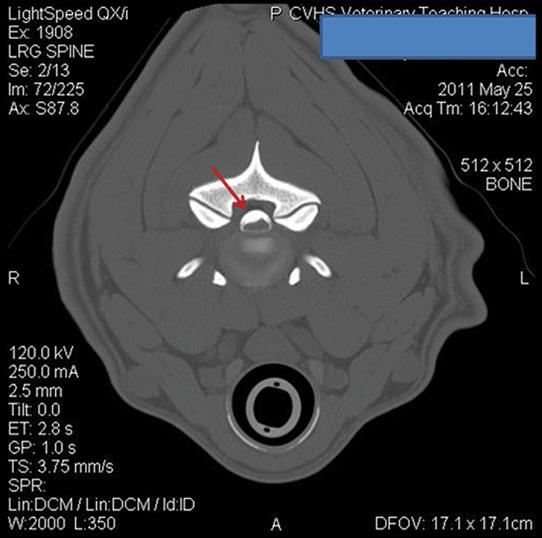

The Fourakers took Cuda to the Center for Veterinary Specialty Care in Fort Worth, where he underwent an MRI. Veterinarians found a cyst on top of the spinal cord between the second and third cervical vertebrae. Veterinarians told the Fourakers surgery was the only option. It would be a delicate procedure with significant risks and an unknown longterm prognosis.

Based on findings of an MRI, OSU anesthetized Cuda and performed tests suggesting the dog’s condition was complicated by additional abnormalities in the cervical vertebrae that may cause future problems.

arrows identify the lesion on cuda’s spinal cord.